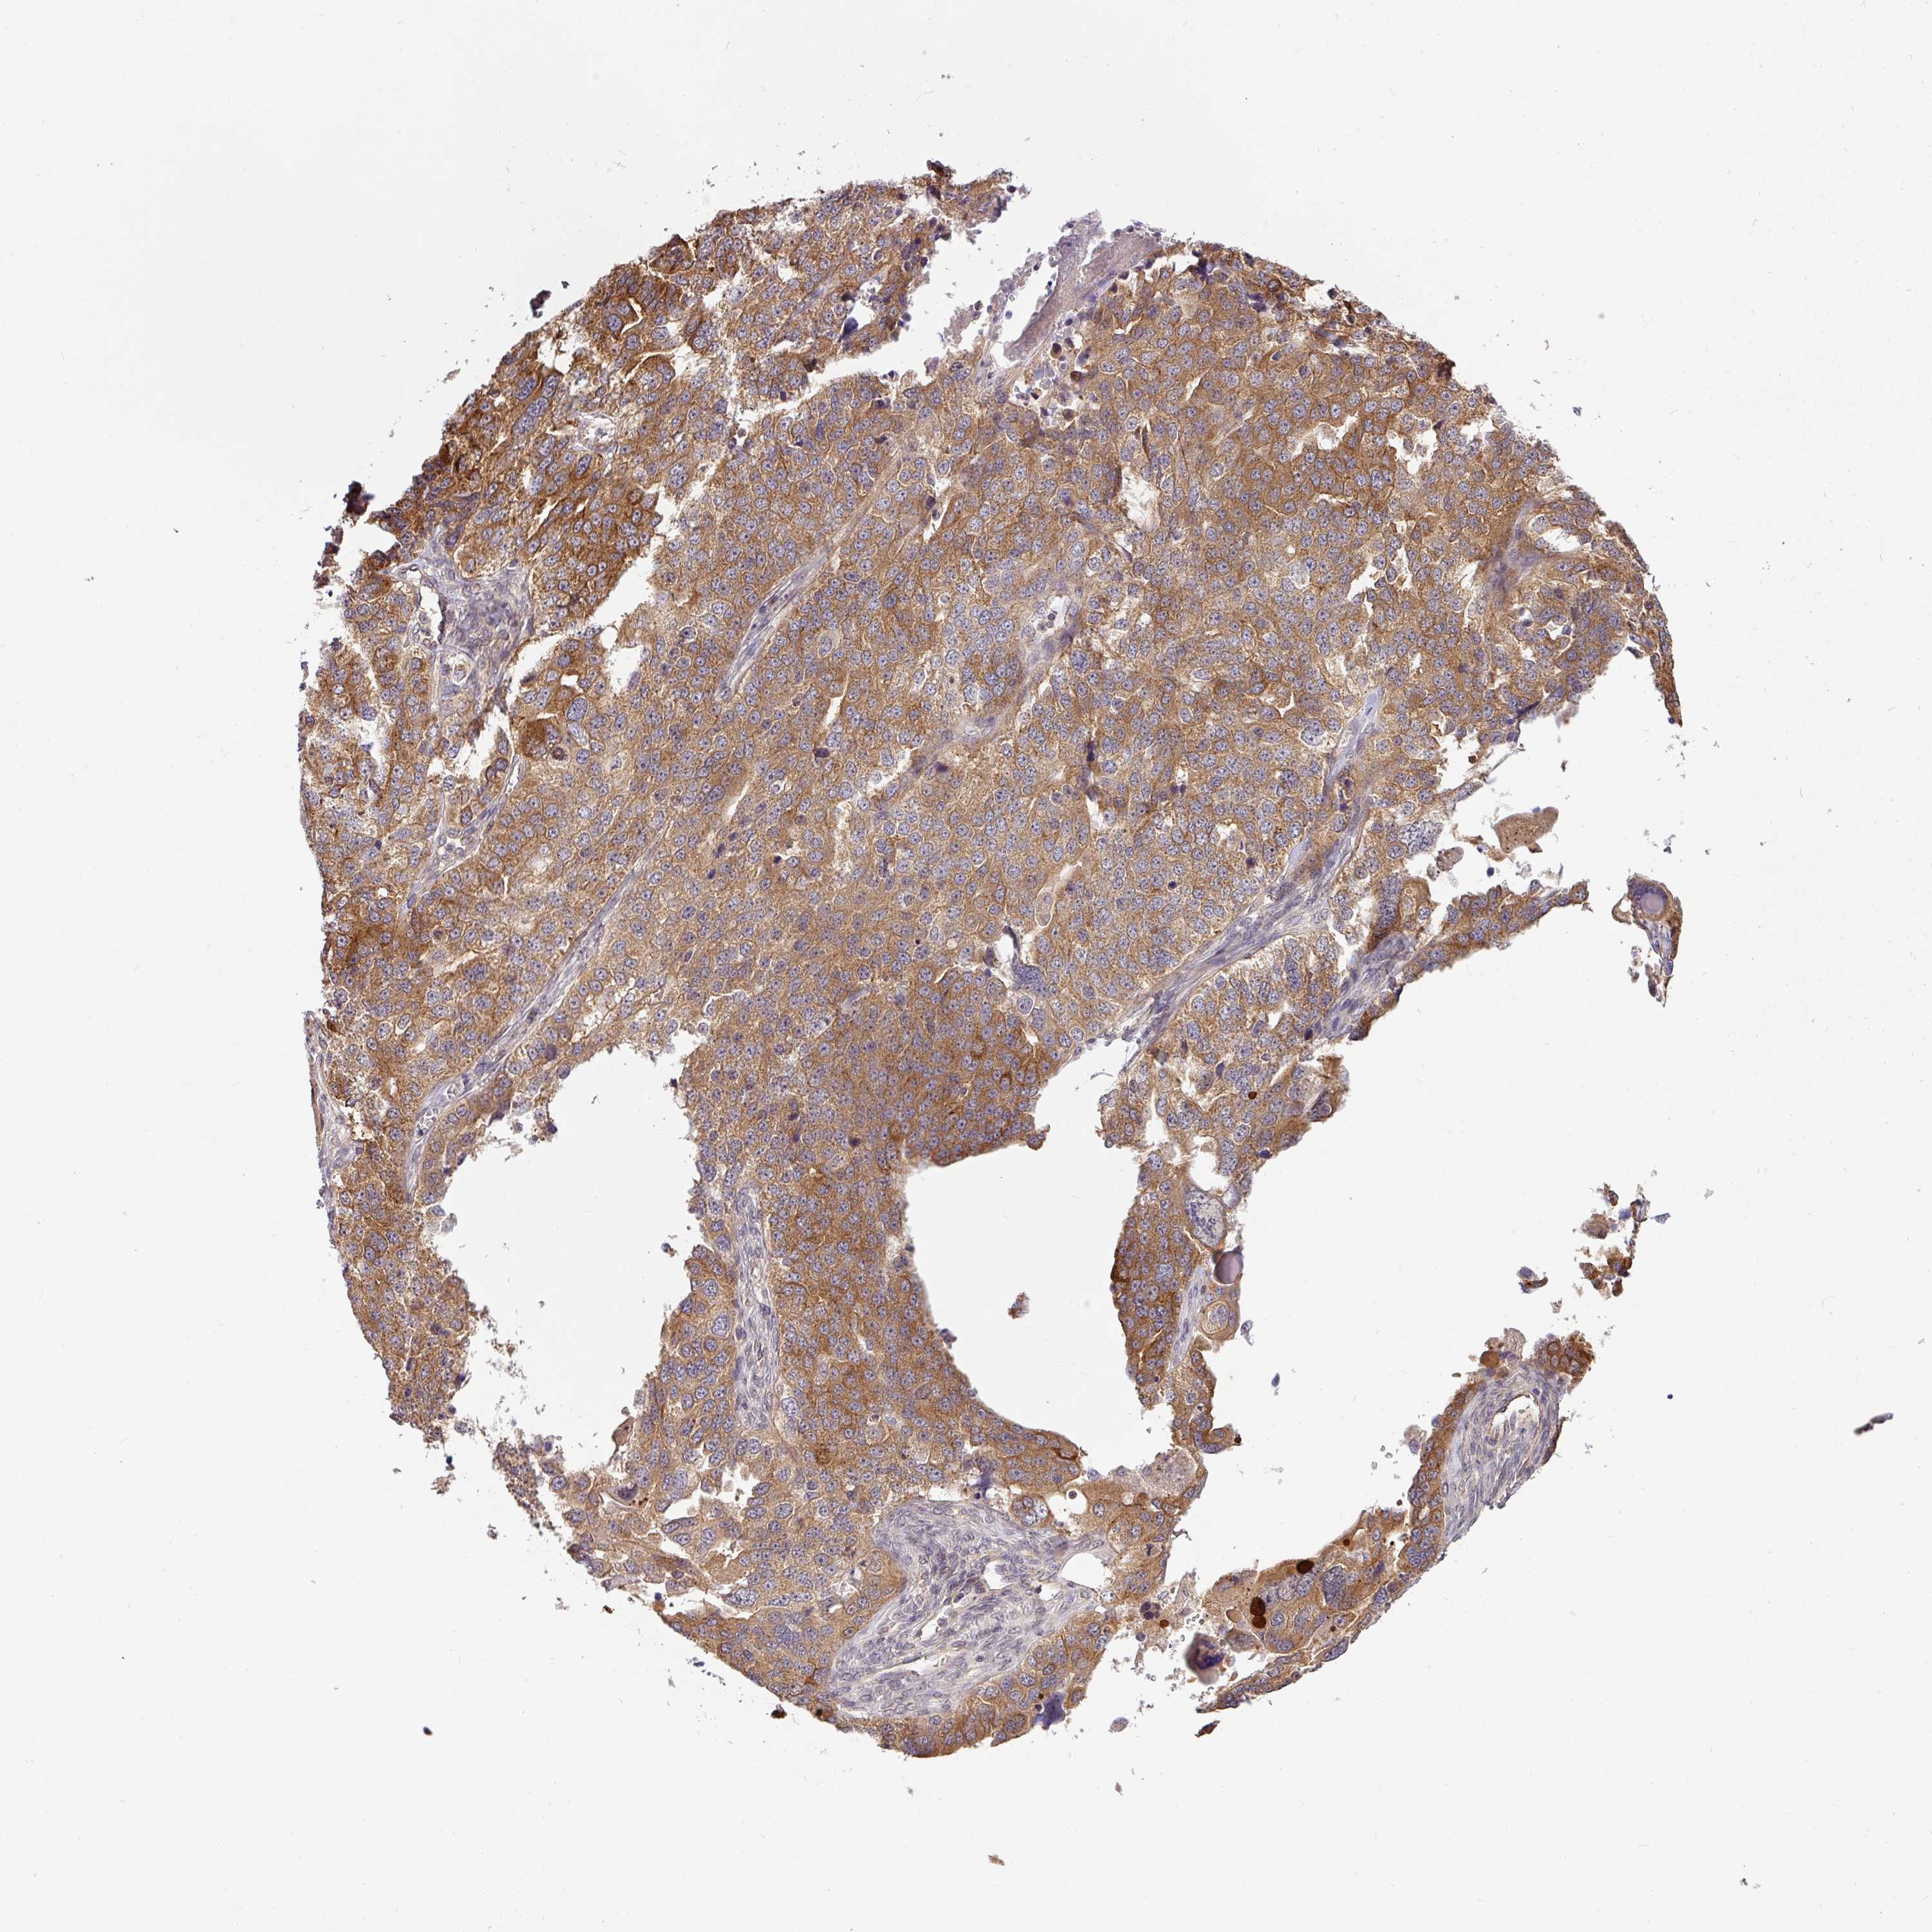

OVARIAN CANCER - Protein expressioni

A mouse-over function shows sample information and annotation data. Click on an image to view it in a full screen mode. Samples can be filtered based on level of antibody staining by selecting one or several of the following categories: high, medium, low and not detected. The assay and annotation is described here.

Note that samples used for immunohistochemistry by the Human Protein Atlas do not correspond to samples in the TCGA dataset.

Antibody stainingi

Antibody staining in the annotated cell types in the current human tissue is reported as not detected, low, medium, or high, based on conventional immunohistochemistry profiling in selected tissues. This score is based on the combination of the staining intensity and fraction of stained cells.

Each image is clickable and will lead to virtual microscopy that enables deeper exploration of all samples and also displays staining intensity scores, fraction scores and subcellular localization as well as patient and tissue information for each sample.

Antibody HPA049911

Antibody CAB010161

Cystadenocarcinoma, serous, NOS

Cystadenocarcinoma, mucinous, NOS

Adenocarcinoma, NOS

Carcinoma, endometroid

Carcinoma, NOS